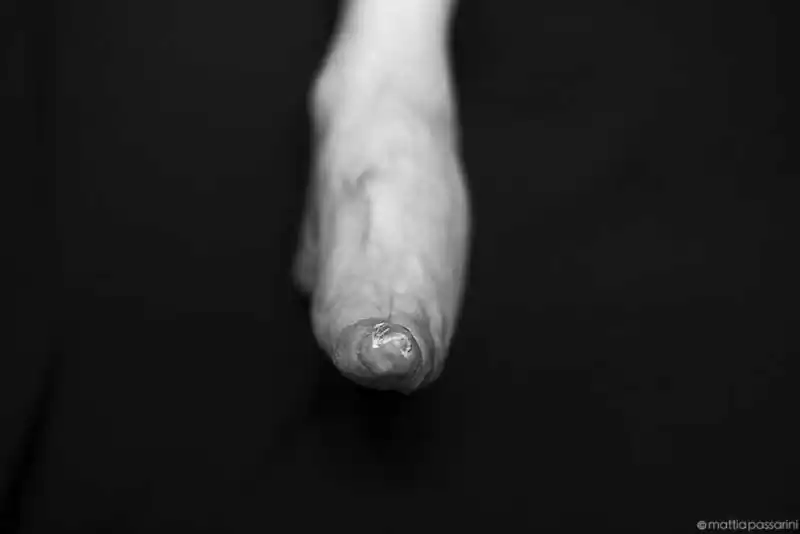

Foot binding became popular as a means of displaying status (women from wealthy families who did not need them to work could afford to have their feet bound) and was correspondingly adopted as a symbol of beauty in Chinese culture and was also a prerequisite for finding a rich husband for poorer women. The process was started before the arch of the foot had a chance to develop fully usually between the ages of 2 and 5. First, each foot would be soaked in a warm mixture of herbs and animal blood, this was intended to soften the foot and aid the binding. Then, the toenails were cut back as far as possible to prevent in-growth and subsequent infections, since the toes were to be pressed tightly into the sole of the foot. To enable the size of the feet to be reduced, the toes on each foot were curled under, then pressed with great force downwards and squeezed into the sole of the foot until the toes broke. When unbound, the broken feet were also kneaded to soften them and the soles of the girl’s feet were often beaten to make the joints and broken bones more flexible. All the process to have a final nice looking binding foot took almost two years. An attribute of a woman with bound feet was the limitation of her mobility, and therefore, her inability to take part in politics, social life and the world. Bound feet rendered women dependent on their men, and became an alluring symbol of chastity and male ownership. In 1912, the new government of China banned foot binding. Since the beginning of this practice over 300 million women have had the foot bound, now just few elderly Chinese women still survive today. [Official Website]